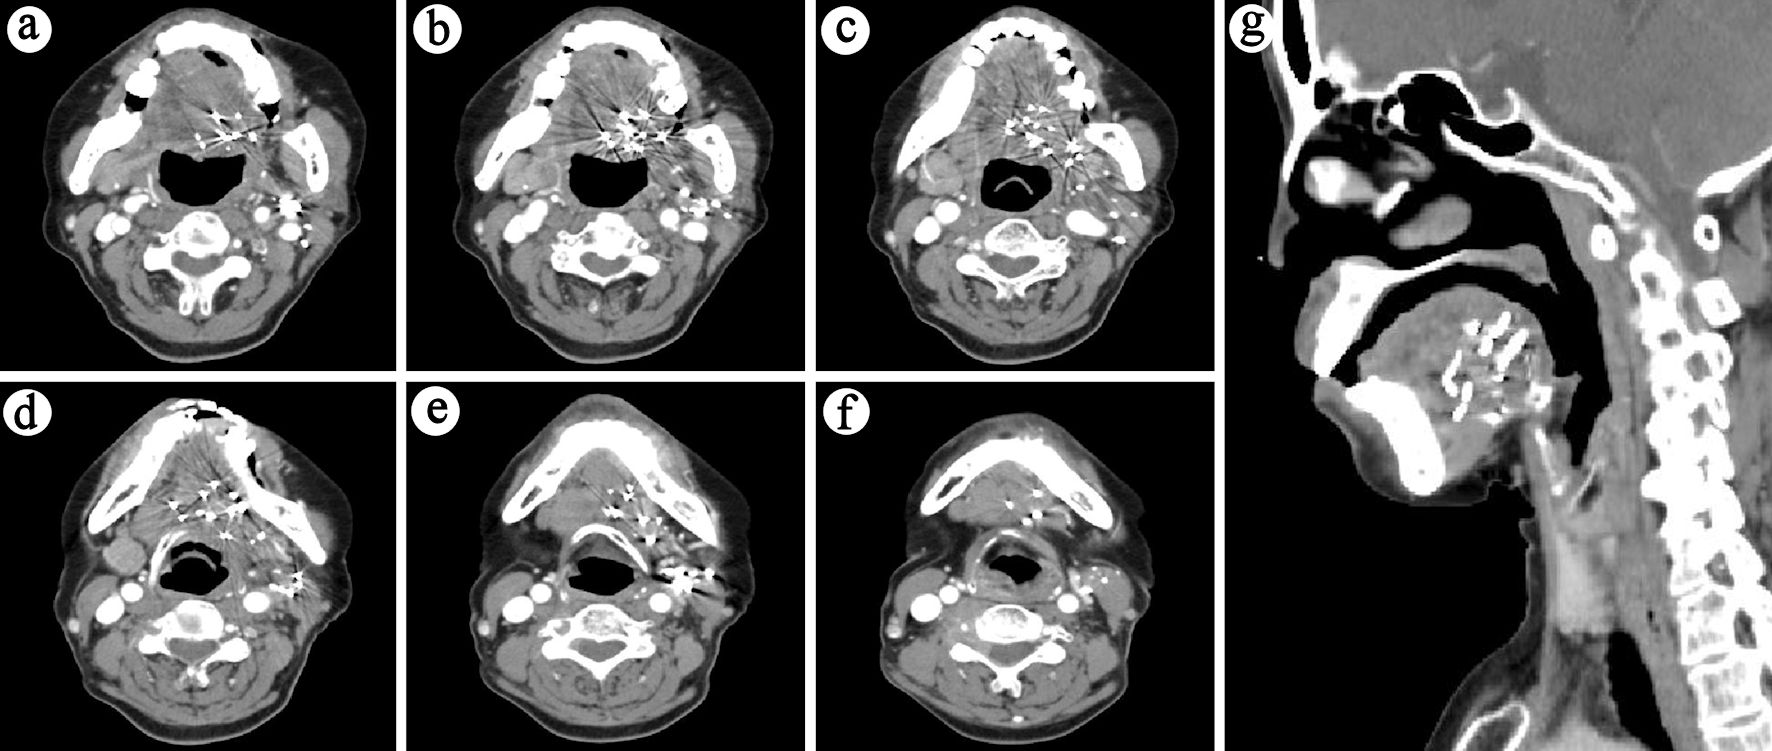

Patients were evaluated 1 month after seed implantation, then every 3 months for the first year, and every 6 months thereafter. Figure 2 shows the follow-up results of a typical case. Our primary objective was to determine local control (LC) and quality of life (QOL), and secondary objectives included the evaluation of overall survival (OS), disease control (DC) and toxicity. LC, DC and OS were defined as the duration from implantation to local recurrence, disease progression and death from any cause, respectively. Toxicities were graded using the Radiation Therapy Oncology Group (RTOG) scoring criteria [11]. QOL was assessed at baseline and 6 months post-treatment using the University of Washington Quality of Life Questionnaire version 4 (UW-QOL-v4), which is a widely used instrument specifically designed for patients with head and neck cancer [12]. The UW-QOL-v4 has 12 domain-specific questions concerning pain, appearance, activity, recreation, swallowing, chewing, speech, shoulder function, taste, saliva, mood, and anxiety. Each item was scored from 0 (worst) to 100 (best).

![]() Click for large image | Figure 2. Six-month post-treatment follow-up CT (lesion no longer evident): (a-f) Sequential cross-sectional views of the lesion. (g) Sagittal view of the lesion. |